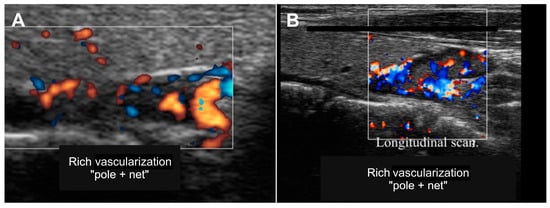

The high vascularization of the parathyroid glands helps differentiate them from lymph nodes and thyroid nodules. Indeed, the lymph nodes present vascularization with hilus located centrally or paracentrally, while the parathyroids show a peripheral arterial pole usually associated with a reticular parenchymal vascularization (Figure 2).

Figure 2. Ecocolor-Doppler US images of parathyroids (white rectangle), showing well-vascularized arterial pole (A) and arterial reticular pattern (B).